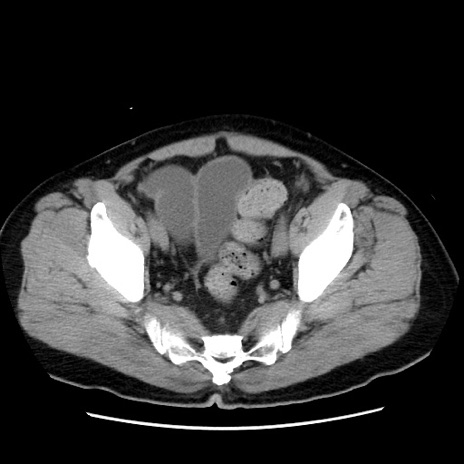

症例16(横断像)

【症例】 70歳代男性

【主訴】 腹痛、嘔吐

【現病歴】 約1ヶ月前より間欠的に腹痛と嘔吐あり、当院消化器内科を受診したところCTで多発する肝臓のLDAを指摘され、精査中であった。以降は消化器症状は安定していたが、2日前より嘔気と腹痛があり、同日より排便・排ガスが消失した。改善認めず、 本日、救急外来を受診した。

【既往歴】 大腸ポリープ切除後。

【身体所見】意識清明・会話良好、BT 36.3℃、BP 127/80mmHg、 P 80bpm、腹部:膨満あり、平坦・軟、上腹部正中および下腹部正中に圧痛あり、反跳痛なし、筋性防御なし。

【データ】WBC 7200、CRP 0.77